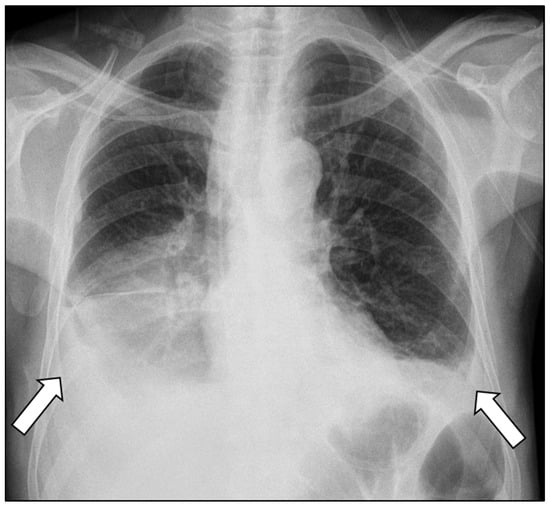

Chest radiography revealed bilateral pleural effusions, more pronounced on the right side (Figure 1). Contrast-enhanced thoracoabdominal computed tomography (CT) confirmed bilateral pleural effusions with associated ascites (Figure 2). The pancreas appeared atrophic with dilatation of the main pancreatic duct, consistent with chronic pancreatitis. A peripancreatic fluid collection extended toward the esophageal hiatus, coursing into the mediastinum and pleural spaces. Magnetic resonance imaging (MRI) confirmed pancreatic atrophy, while magnetic resonance cholangiopancreatography demonstrated an irregularly dilated main pancreatic duct measuring approximately 1 cm with intraductal filling defects. A fistulous tract originating from the pancreatic body and extending through the left side of the esophageal hiatus into the mediastinum was identified. The biliary tree and gallbladder were unremarkable, and no further pancreatic lesions were appreciated (Figure 3), thus not necessitating further evaluation with EUS. These findings established the diagnosis of chronic calculous pancreatitis complicated by a pancreaticopleural fistula. As imaging studies took place promptly following initial presentation, and the suspicion of pancreaticopleural fistula was established early, pleural fluid amylase levels were not sent for this patient.

Figure 1.

Chest radiograph demonstrating bilateral pleural effusions (arrows), more pronounced on the right side.